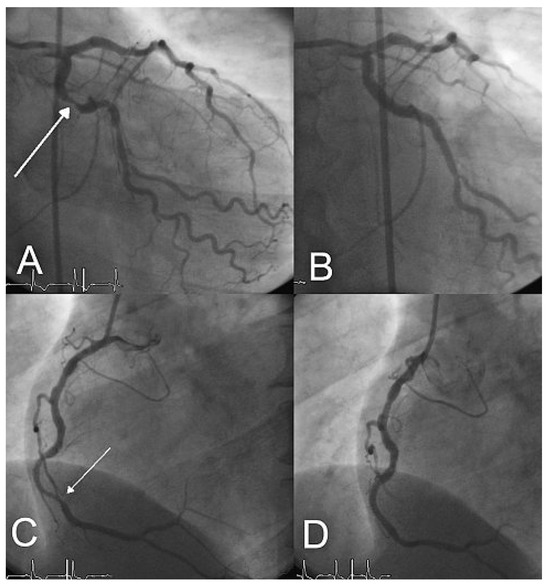

New Amplatzer Duct Occluder II for Antegrade Closure of Patent Ductus Arteriosus

by Stéphane Cook, Tobias Rutz and Bernhard Meier

Cardiovasc. Med. 2009, 12(11), 313; https://doi.org/10.4414/cvm.2009.01457 - 13 Nov 2009

Transcatheter closure of patent ductus arteriosus is a safe and effective technique. The new version of the Amplatzer PDA occluder (Amplatzer Duct Occluder II) permits antegrade delivery and significantly simplifies the procedure. Full article